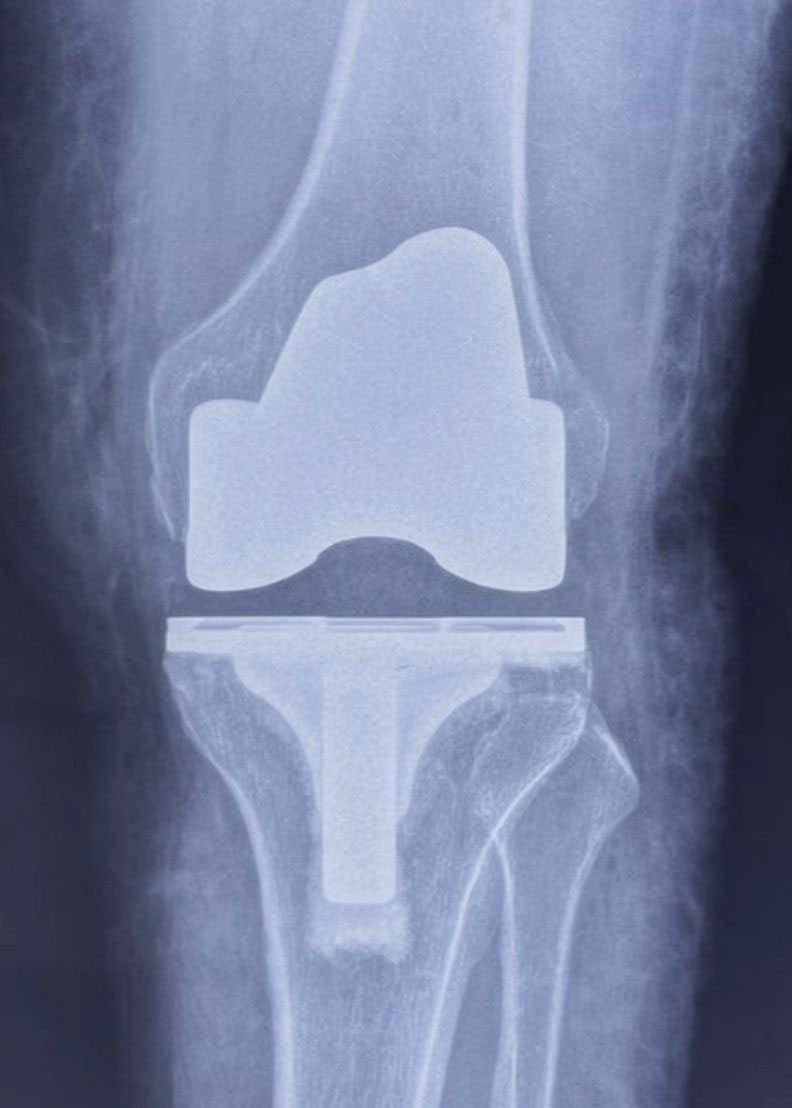

'Total Knee Replacement' is a misleading term as your whole knee is not replaced!

It only involves resurfacing the cartilage on the bones with new surfaces made of metal and polyethylene, which have been used successfully for many years.

In the normal knee, the bones are covered with a thin white cushion called cartilage, which prevents the bones from rubbing against one another.